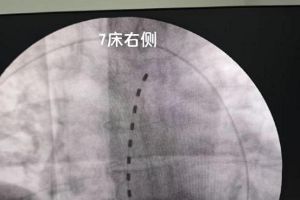

玉医:血液净化中心通过扩建验收 区域血透服务能力再升级

2025年5月8日,按照《云南省卫生健康委办公室关于进一步加强血液透析管理工作的通知》,云南省医疗服务质量评估中心组织省级专家组,对玉溪市人民医院肾内科血液净化中心扩建项目开展专项验收。此次验收通过后,该中心将为区域内肾病患者提供更优质、更高效的医疗服务。